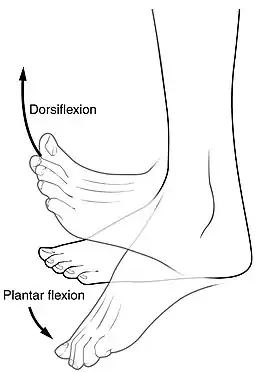

Plantar fasciitis is usually diagnosed by a health care provider after consideration of a person's presenting history, risk factors, and clinical examination.[4][16][17] Palpation along the inner aspect of the heel bone on the sole may elicit tenderness during the physical examination.[4][11] The foot may have limited dorsiflexion due to excessive tightness of the calf muscles or the Achilles tendon.[7] Dorsiflexion of the foot may elicit the pain due to stretching of the plantar fascia with this motion.[4][12] Diagnostic imaging studies are not usually needed to diagnose plantar fasciitis.[7] Occasionally, a physician may decide imaging studies (such as X-rays, diagnostic ultrasound, or MRI) are warranted to rule out serious causes of foot pain.